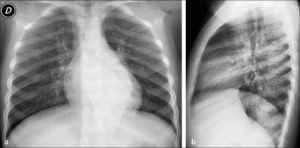

Este compromiso se observa en Rx simple como aparición de opacidades peribronquiales que adoptan un aspecto radiado desde el hilio pulmonar hacia la periferia; la medida que estos cambios progresan, el patrón se hace más confluente. La presencia de edema e infiltrados celulares en los espacios peribronquiales produce disminución de calibre y obstrucción de la vía aérea, lo que determina aparición de dos hallazgos importantes que habitualmente se asocian a la neumopatía intersticial: hiperinsuflación y atelectasias (1).

La hiperinsuflación es consecuencia del mecanismo de válvula que se produce en espiración en la vía aérea inflamada, hecho que se acentúa en la edad pediátrica por su escaso calibre, generando atrapamiento aéreo con aumento de la transparencia del parénquima pulmonar. La proyección lateral es de gran utilidad para valorar el aumento del diámetro antero-posterior, aplanamiento diafragmático y aumento de transparencia del espacio retroesternal, como signos de hiperinsuflación (Figura 7). En los niños es frecuente observar atelectasias, especialmente subsegmentarias, por el menor desarrollo de la ventilación colateral en el pulmón infantil (canales de Lambert y poros de Kohn). Estas atelectasias aparecen como bandas lineales, densas, pequeñas, de contornos bien definidos, visibles especialmente en las regiones medias inferiores de los pulmones. En niños mayores es posible observar también atelectasias segmentarias o lobares, con un patrón anatómico similar al que se observa en adultos (4).